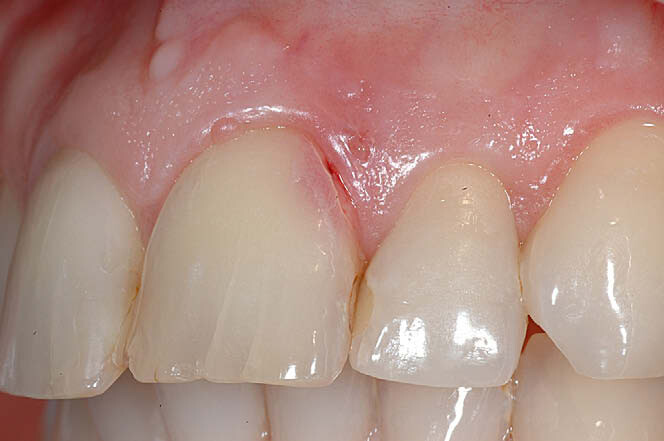

External cervical resorption

External cervical resorption (ECR) is a type of external resorption that begins at or near the cementoenamel junction. Typically, patients present asymptomatic, and the lesion is simply discovered on routine exams or at prophylactic appointments. This type of resorption can occur in any type of tooth throughout the mouth. Still, a higher percentage of these lesions is noted in the maxillary anterior teeth and the maxillary and mandibular first molars.

For this type of resorption to occur, some type of damage has happened to the periodontal ligament and protective cemental layer in that area. Factors such as trauma, orthodontics, bleaching, periodontal surgery, and therapy can predispose the patient to this resorptive process. Even the transmission of feline herpesvirus and herpes zoster virus has been mentioned as a possible cause. So don’t forget to check those fur babies, because felines can present with resorptive issues on their teeth too!

ECR can be differentiated from root caries due to its pink hue and tactile sensation. During the examination, you will find that the dentin surrounding an ECR lesion is usually hard, whereas decay/caries typically feels sticky. When a clinician performs probing around this type of lesion, it will typically bleed—often profusely—because of the highly vascular granulation tissue, a result of the resorptive process.

Schwartz et al. described the process, noting that “osteoclasts initially penetrate the tooth through a small entry point and colonize this region. Clastic cells in association with fibrovascular tissue then spread in a circumferential and apicocoronal direction around the root canal system. Numerous irregular resorptive channels are created that can interconnect apically with the periodontal ligament.” If caught early enough, removal of the granulation tissue and restoration may be sufficient to resolve the issue. More invasive resorptive processes sometimes involve trichloroacetic acid treatment for the resorptive lesion, root canal therapy, surgery, or even loss of the tooth to correct.